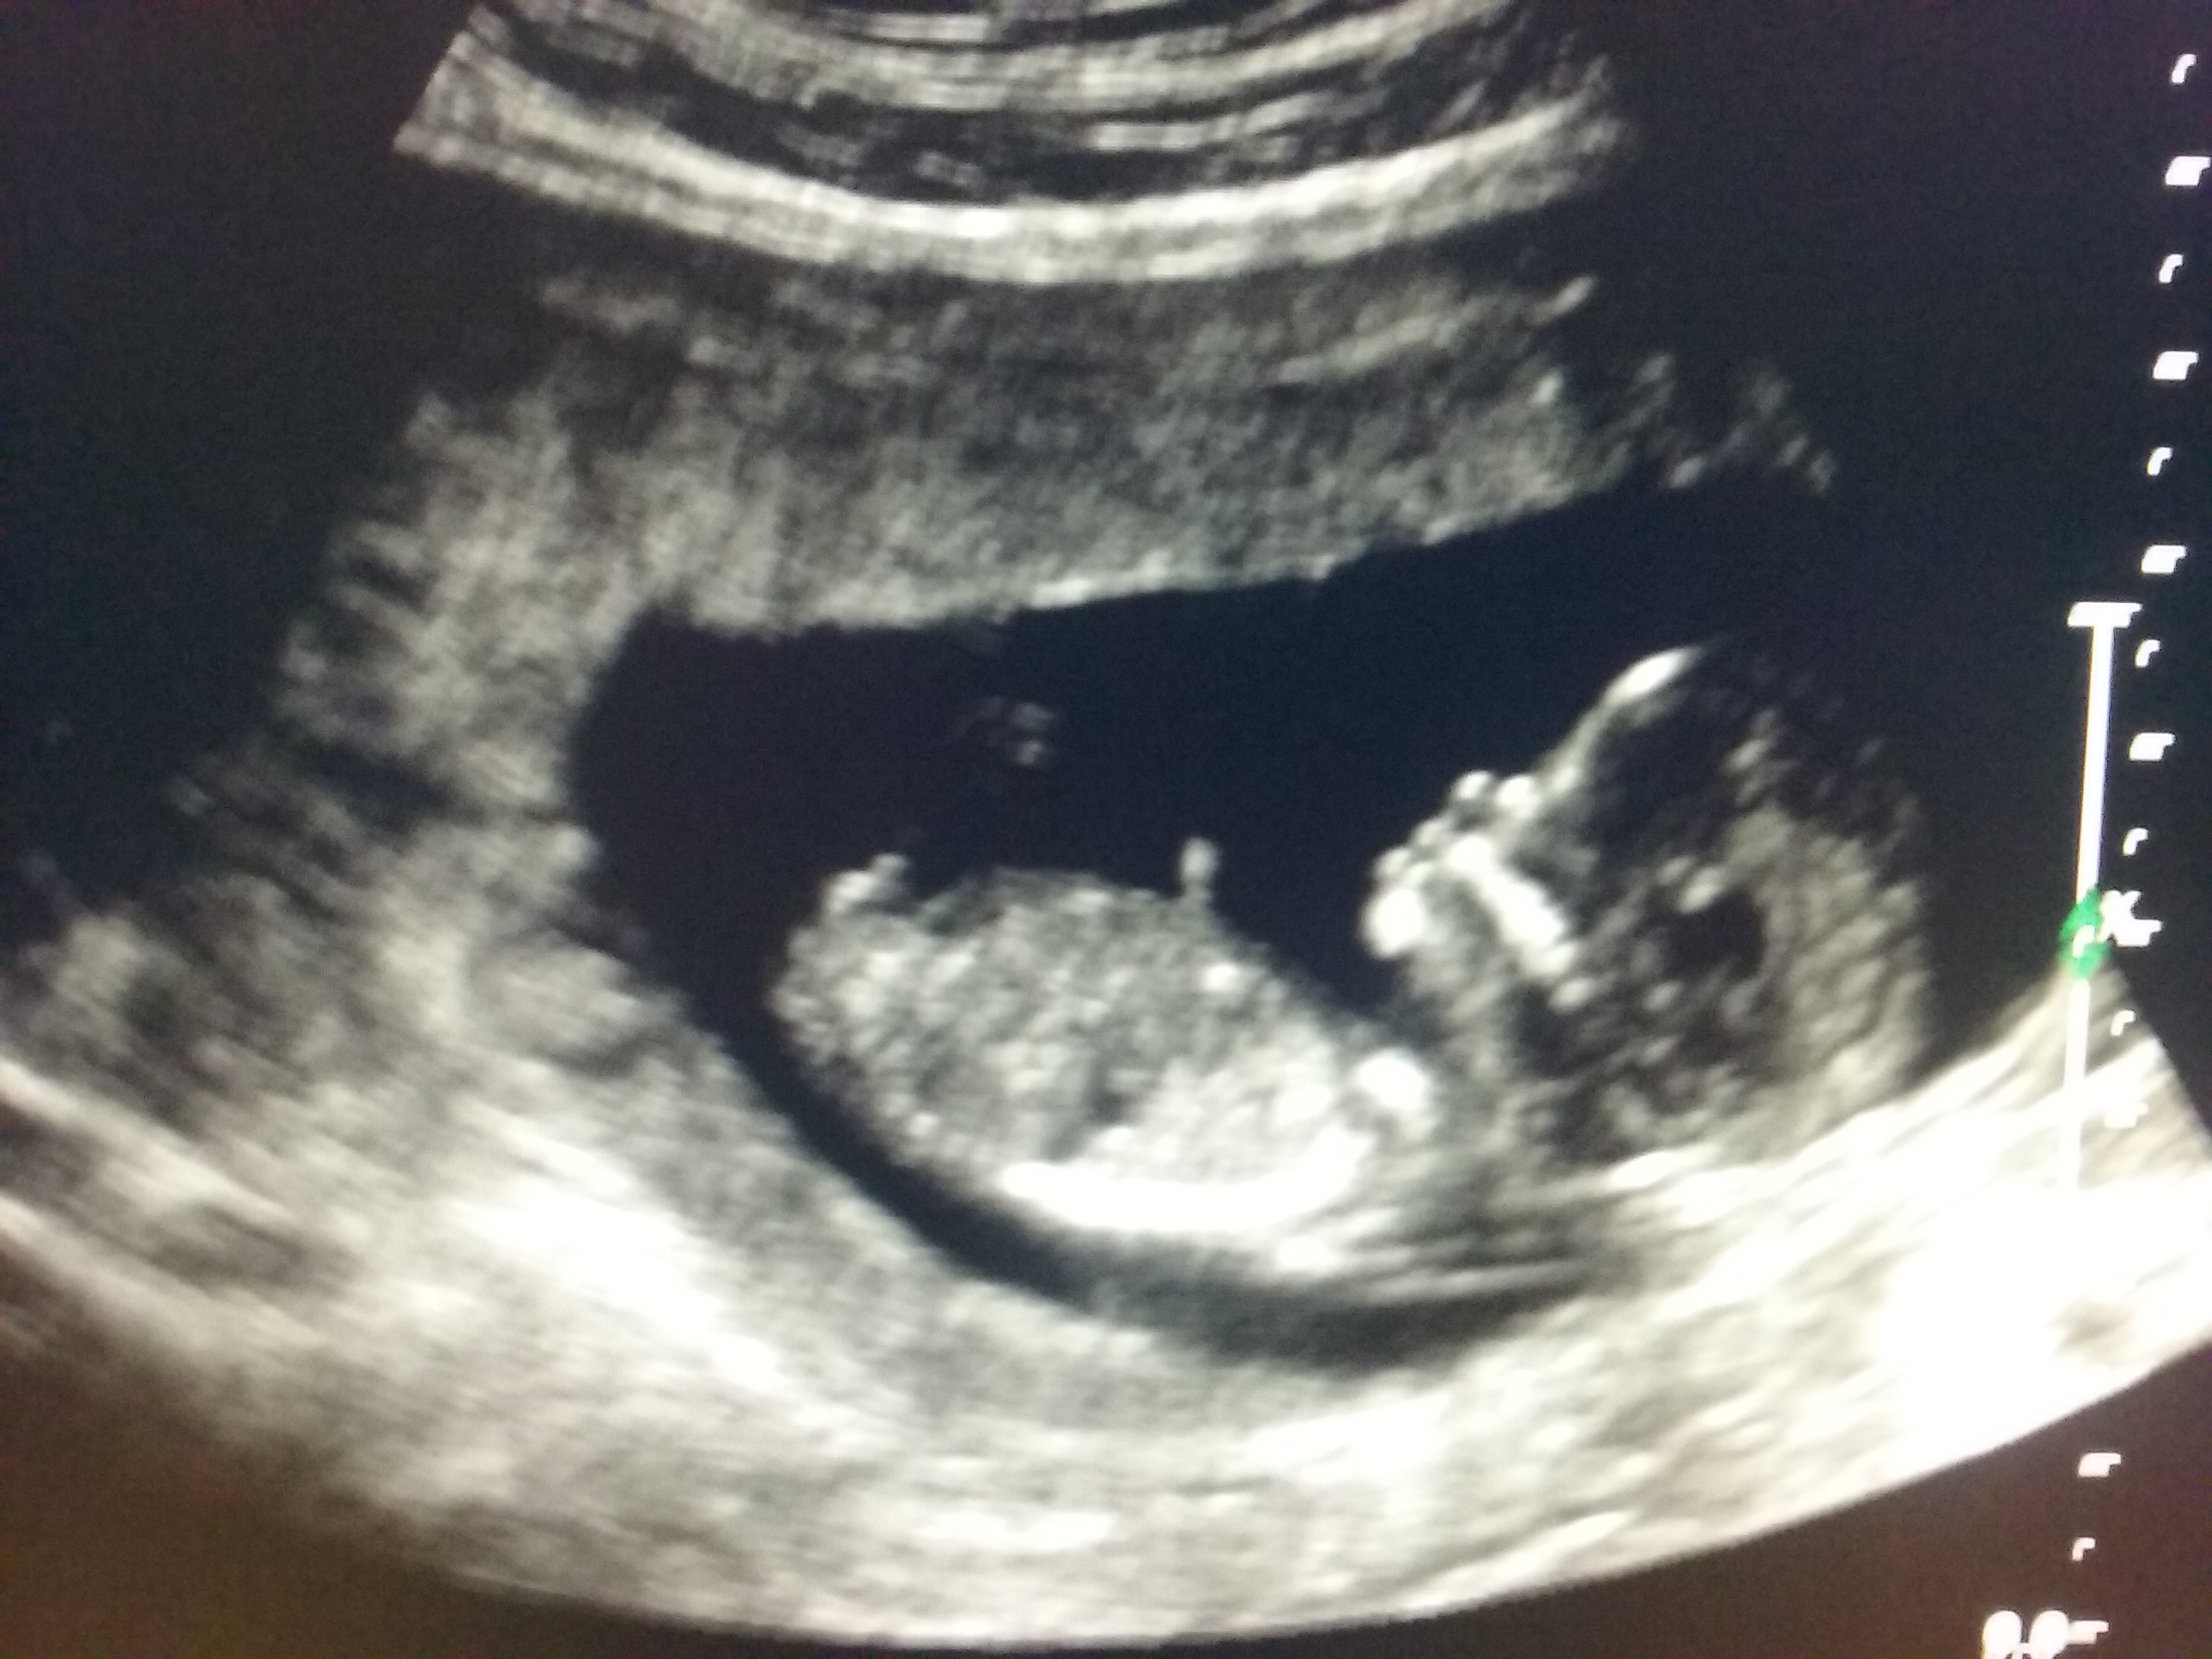

Hello, I went for my 12 week scan today and was hoping to get some pics of the nub but these are the only pics I could get from the sonographers screen so I thought I would post here for some advice, can you see a nub or what do you think based on the skull theory? Thank you